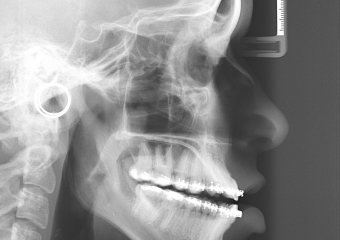

Telerradiografia inicial